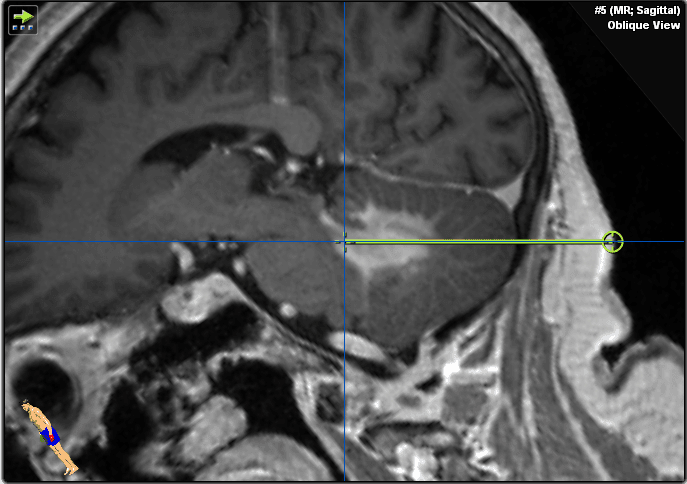

Ha effettuato una risonanza magnetica che ha mostrato una lesione omogenea con contrasto adiacente al quarto ventricolo nel tessuto cerebellare e un edema perifocale moderato (Figure 1–2). I peduncoli del tronco encefalico e cerebellari non erano coinvolti. Non sono stati rilevati segni di emorragia o ischemia.

Figura 1. Queste immagini ponderate T1 potenziate dal gadolinio mostrano una lesione infratentoriale nel cervelletto e nel peduncolo cerebellare sinistro adiacente al quarto ventricolo. Si prega di notare l'aumento omogeneo del contrasto sospetto di linfoma del SNC e mancanza di infiltrazione del tronco encefalico.